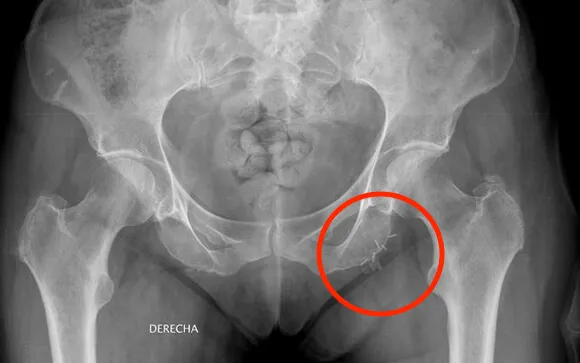

Radiography of the abdomen of a patient with remains of poor quality needles:

"The problem is that the elections are every four years, and politicians do not look beyond that space of time" the first vice president of this patient group, Aureliano Ruiz exposes, in statements to consalud.es, that many patients lookForced to use “poor quality” needles that, even often, break falling inside the patient's abdomen.In addition, they warn of the pain they cause during use.